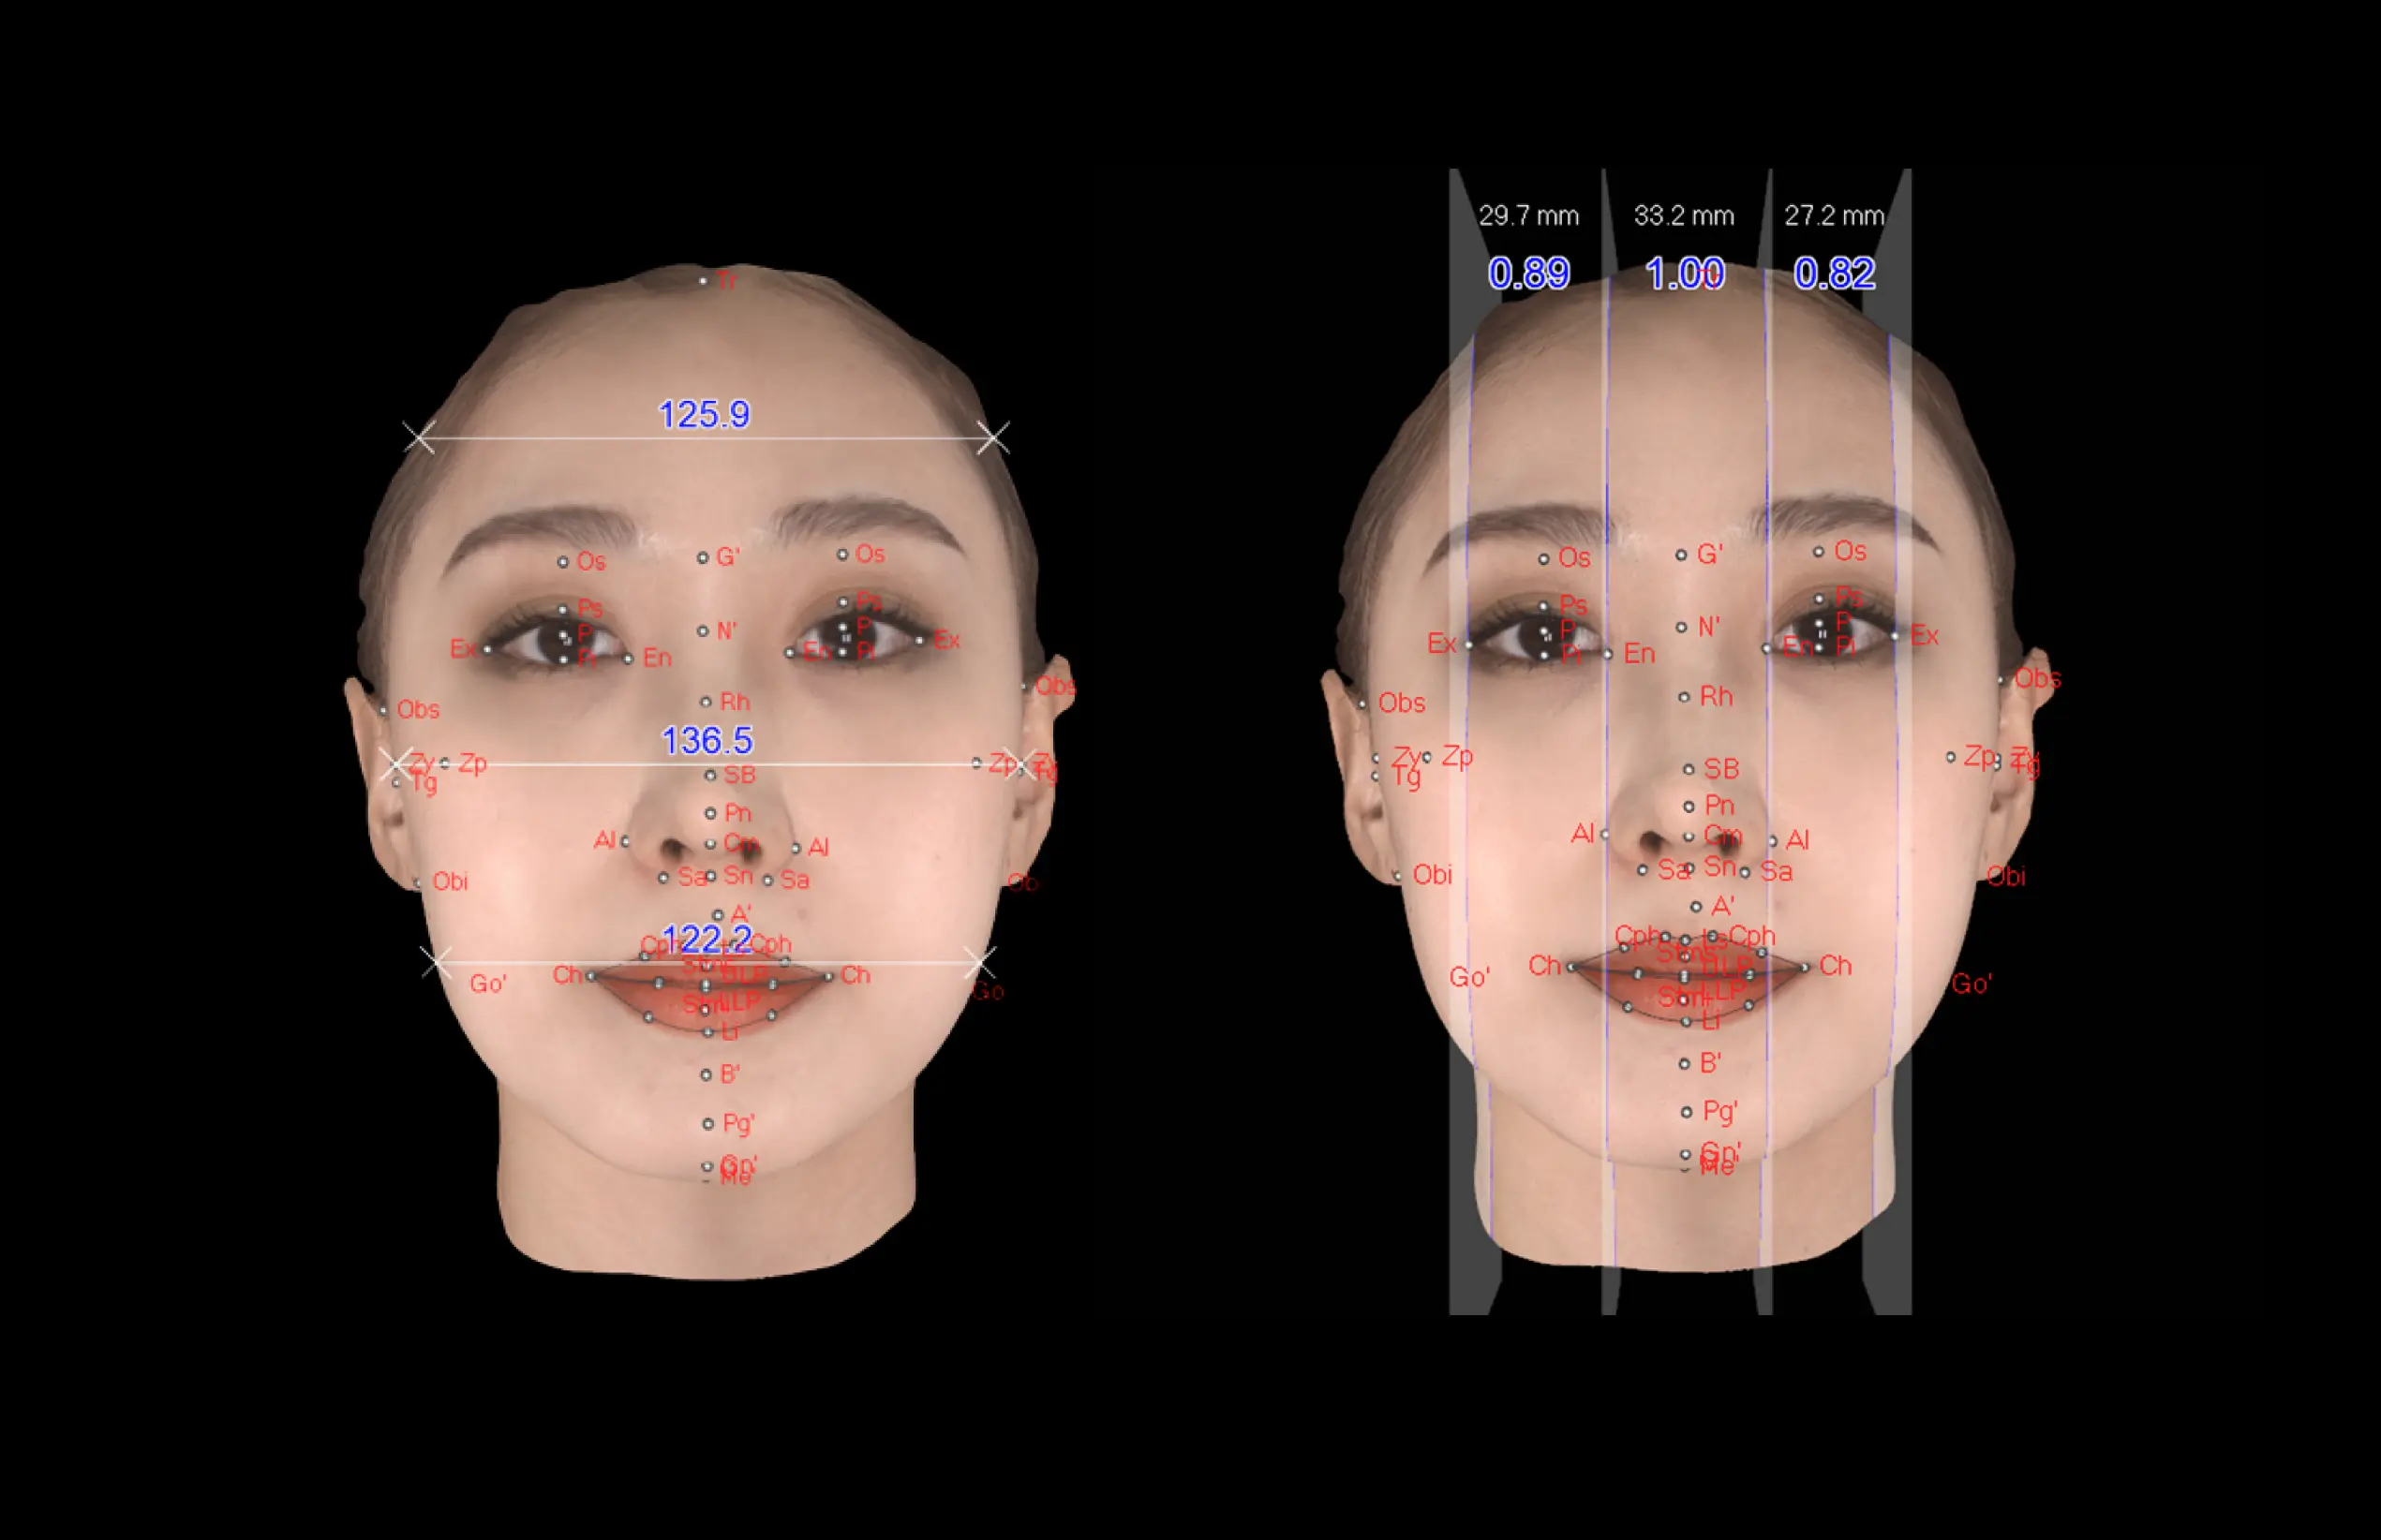

더보기 눈과 미간의 균형

·얼굴 상안, 중안, 하안의 직선 너비

·안각간 거리와 좌·우안 거리의 비율을 측정

하는 수평적 분석